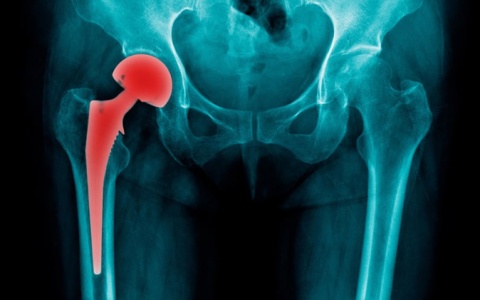

Qua thăm khám lâm sàng và cận lâm sàng, bệnh nhân được chẩn đoán chấn thương háng phải – gãy cổ xương đùi phải. Sau khi hội chẩn liên chuyên khoa và đánh giá toàn trạng, ekip bác sĩ Ngoại Chấn thương đã quyết định tiến hành phẫu thuật thay khớp háng bán phần.

Nhờ kỹ thuật chuyên môn cao và quy trình phẫu thuật chính xác, ca mổ đã diễn ra thuận lợi và thành công. Sau phẫu thuật, bệnh nhân được tập các bài vận động của khoa Y học Cổ truyền – Phục hồi chức năng, giúp phục hồi chức năng vận động háng phải, giảm đau và rút ngắn thời gian nằm viện.

Sau quá trình điều trị kết hợp, bệnh nhân đã có tiến triển tốt, đi lại được với sự hỗ trợ của dụng cụ và đã xuất viện trong tình trạng ổn định.